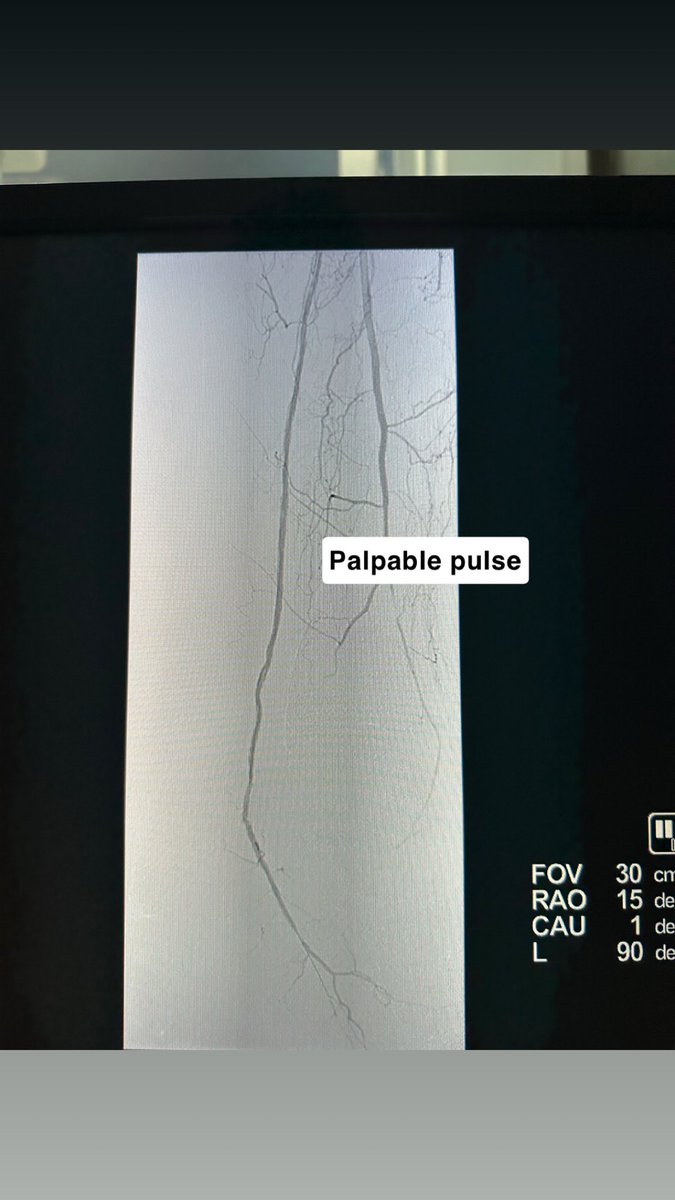

تقنيات #الأشعة_التداخلية ساهمت بفضل الله في إعادة التروية للقدم المصابة بجروح السكري والغرغرينا، مما ساعد بشكل مباشر وغير مباشر في الحفاظ على الأطراف وتقليل الحاجة للبتر، وتحسين جودة الحياة للمريض وعائلته. تُجرى الإجراءات عادةً تحت تخدير موضعي مع إمكانية الخروج في نفس اليوم.

الدكتور حسان المقبل: الآن يوجد علاج للغرغرينه ولله الحمد والا داعي للبتر بإذن الله. #هزة_أرضية #زلزال